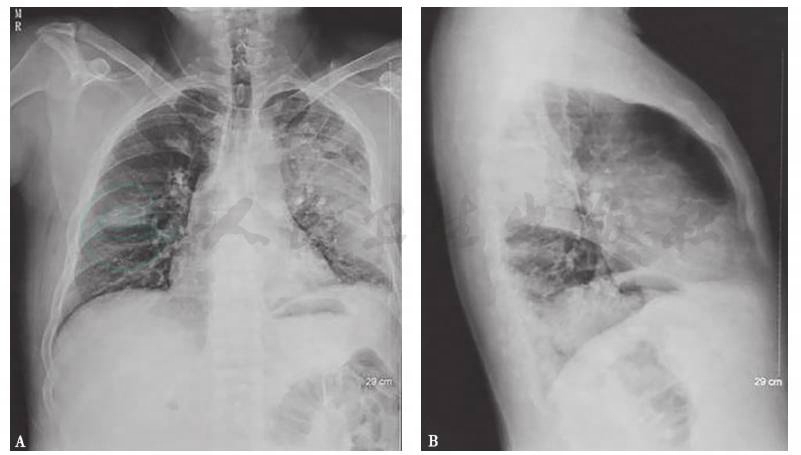

入院前20天X线胸片:双肺纹理增重,右肺中野可见团片状高密度模糊影,边界不清,左肺可见大片高密度模糊影;双肺门不大,纵隔居中,心影不大;两膈光滑,双侧肋膈角锐利(图2)。

图2 入院前20天X线胸片

X线胸片可见右肺中野片状边缘模糊渗出影,左肺上叶后段及左下肺可见大片高密度模糊影

胸部X线片:双肺纹理增重;右肺中野可见团片状高密度模糊影,边界不清;左肺可见大片高密度模糊影;双肺门不大,纵隔居中,心影不大;两膈光滑,双侧肋膈角锐利(图5)。

图5 入院后X线胸片

X线胸片示双肺纹理增重,右肺中野可见团片状高密度模糊影,边界不清,左肺可见大片高密度模糊影